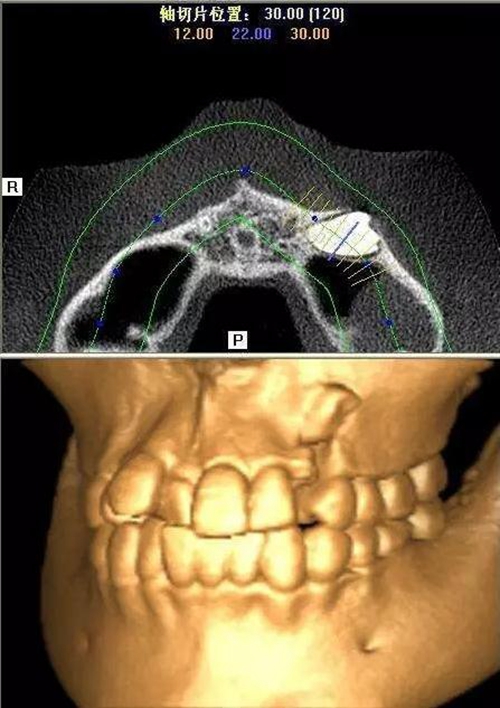

本案:患兒,女,14歲,因牙齒矯正來院,檢查見83滯留,43未見萌出,拍片發(fā)現(xiàn):43埋伏阻生于31、41、42根尖下方,按照正畸診療計(jì)劃,擬行43拔除術(shù)。

CBCT顯示

設(shè)計(jì)冠切的位置